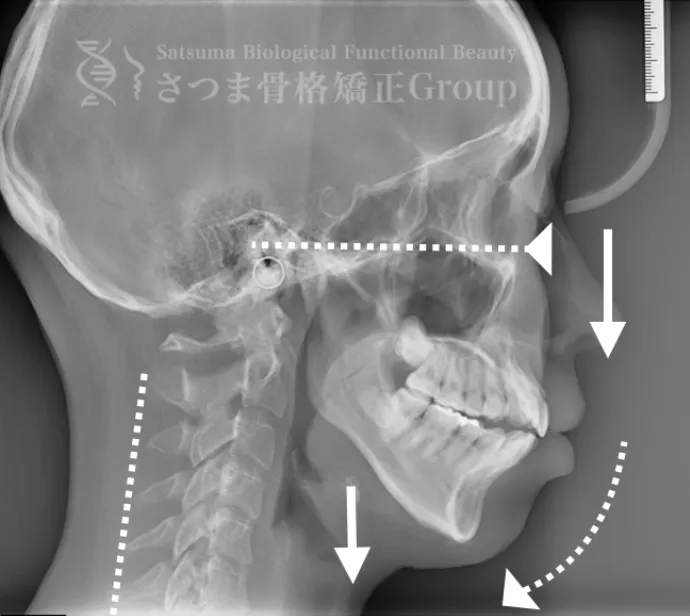

20代女性 M様 初回効果

BEFORE

軽度の顎変形症あり。

下顎の後方回転あり。

中顔面が伸びて下方に落ちる。

中顔面の奥行きを失っている。

頚椎ストレートネック。

Mild jaw deformity present.

Posterior rotation of the mandible.

The midface is elongated and has dropped downward.

Loss of depth in the midface.

Cervical spine straightening (straight neck).

AFTER

咬筋と上部頸椎をリリースさせ、顎の前方回転。

さつま式で中顔面の奥行きを作り、短縮。頸部の前湾角の強化。

Release the masseter and upper cervical spine to achieve forward rotation of the jaw.

Using the Satsuma method, create depth in the midface and shorten it.

Enhance the cervical lordosis angle.

AFTER(マウスピース使用時)

整骨後、形成したマウスピースで形と上部頸椎のリリースを維持蝶形骨の

可動をブーストし顔面骨をアライメントから整顔・整骨。

After the osteopathy, the custom-formed mouthpiece maintains the shape and the release of the upper cervical spine, boosts the mobility of the sphenoid bone, and aligns the facial bones for facial correction and structural adjustment.